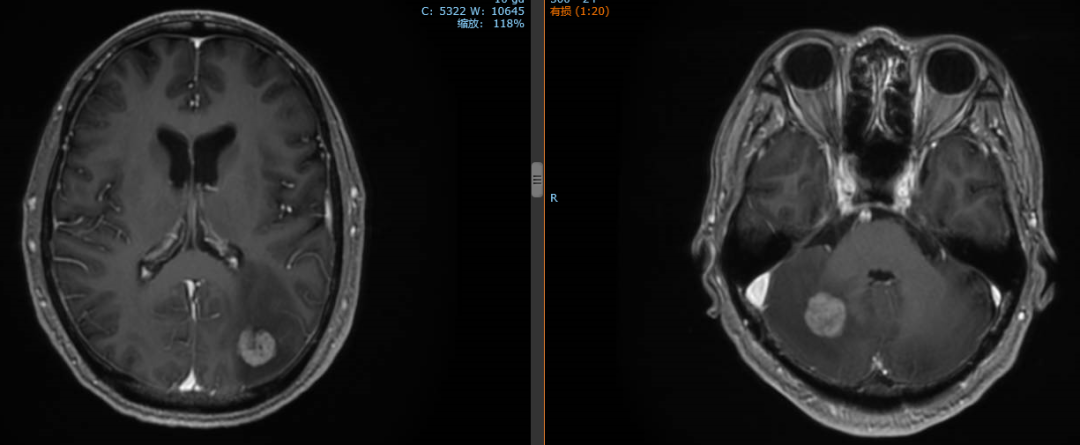

2020年1月患者出现头痛症状,复查脑MR示:枕叶及右侧小脑半球多发结节,结合病史考虑转移灶。

经影像学评估后,患者肝脏、双肺、颈部淋巴结无进展。

2020年1月13日开始对左侧枕叶及右侧小脑转移灶进行放疗,PTV-GTV=44.5Gy/9F

复查:2020.4复查颈部CT及全腹部+盆腔MR大致同前,脑MR示病变较前明显缩小,评估PR。

2020年11月4日复查颈部胸腹盆CT大致同前,脑转移灶明显缩小,继续赫赛汀联合希罗达维持治疗。